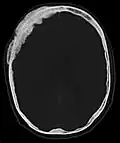

Für die initiale Diagnosestellung hat das konventionelle Röntgenbild eine zentrale Bedeutung. Die Indikation für Aufnahmen in zwei Ebenen ist bei dem Verdacht auf Knochentumoren immer gegeben.[85] Osteolytische Metastasen sind durch eine Abnahme der Knochendichte gekennzeichnet. Dies ist in der Röntgenaufnahme aufgrund der höheren Transparenz für Röntgenstrahlen, durch einen höheren Schwärzungsgrad zu erkennen. Umgekehrt zeigen osteoplastische Metastasen wegen der Zunahme der Knochendichte einen geringeren Schwärzungsgrad. Osteolytische Knochenmetastasen sind an der Wirbelsäule deutlich schwieriger zu erkennen; meist erst dann, wenn bereits etwa 50 % der Gesamtknochenstärke verlorengegangen ist.[85]

-

Axiale Computertomografie einer osteoplastischen Metastase im Schädelknochen eines Patienten mit Prostatakarzinom. Deutlich ist die Ausdehnung der Metastase über die ursprünglichen Knochengrenzen hinaus zu erkennen. -

Im Vergleich dazu eine Computertomografie osteolytischer Metastasen in den Schädelknochen einer Patientin mit Mammakarzinom. Zu sehen ist eine größere Osteolyse frontal und mehrere kleinere. -

Röntgenaufnahme des Beckens eines Patienten mit Prostatakarzinom: Multiple osteoplastische Knochenmetastasen, insbesondere im Kreuzbein, aber auch im Darmbein, vor allem links (also rechts im Bild), am Sitzbeinhöcker links und im proximalen Oberschenkelknochen links. Nebenbefundlich zeigt sich eine Hüftgelenksarthrose rechts (also links im Bild). -

Röntgenaufnahme des Beckenraums osteolytischer Metastasen. Die Metastasen sind in beiden Oberschenkelknochen und am Becken selbst.